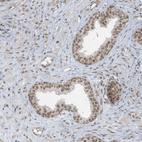

Immunohistochemical staining of human stomach shows moderate to strong nuclear positivity in glandular cells.